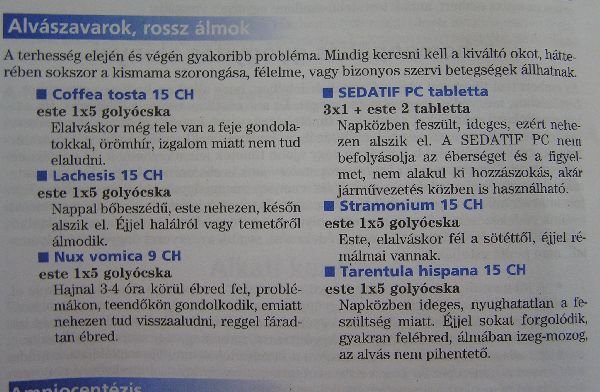

A terhesség utolsó hónapjaiban testi és lelki okok akadályozhatják a nyugodt alvást. A probléma megszüntetéséhez természetes gyógymódokat is igénybe lehet venni.

Az álmatlanság a terhesség egyik tipikus panasza. A helyzet a harmadik trimeszterben lehet a legrosszabb. Ebben az időszakban ugyanis a leendő anyuka szervezete nagy mennyiségű hormont(elsősorban progeszteront) termel, amely módosítja a központi idegrendszer működését, és ezzel izgalmi állapotot idéz elő.